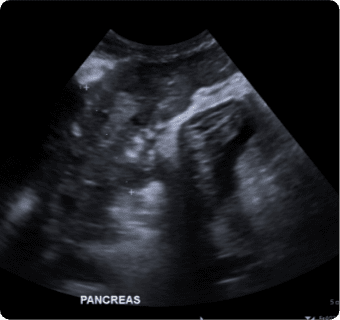

일산시티동물의료센터는 지멘스에서 개발한 고성능 프리미엄 초음파 장비인

Siemens Sequoia를 활용하여 심장, 복부 장기, 림프절 등의 구조물을 선명하게 구현하고,

미세한 해부학적 구조까지 정밀하게 확인할 수 있습니다.

또한 급성 췌장염, 급성 신부전, 자궁축농증, 방광염, 요로결석, 소화기 이물,

비장종양 등의 질환을 진단하고, 환자의 상태를 평가하는 데에도 활용됩니다.